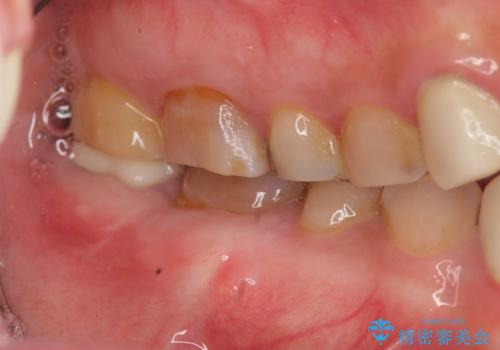

歯ぎしりによる異常に低い歯冠高径 歯周外科による解決

- 右下修復物の破損修復を希望され来院されました。

失活歯であるため根管治療ののちクラウン製作が治療計画として考えられますが長年のすり減りによりクラウン高径がほとんどなくてなってしまっている状態です。

歯周外科を行い歯茎の位置を下げることで安定したクラウン製作ができる状態を目指します。

あまりにもクラウン高径が低いと、安定性が悪くなりセメントの溢出を招き虫歯の再発リスクを高めます。